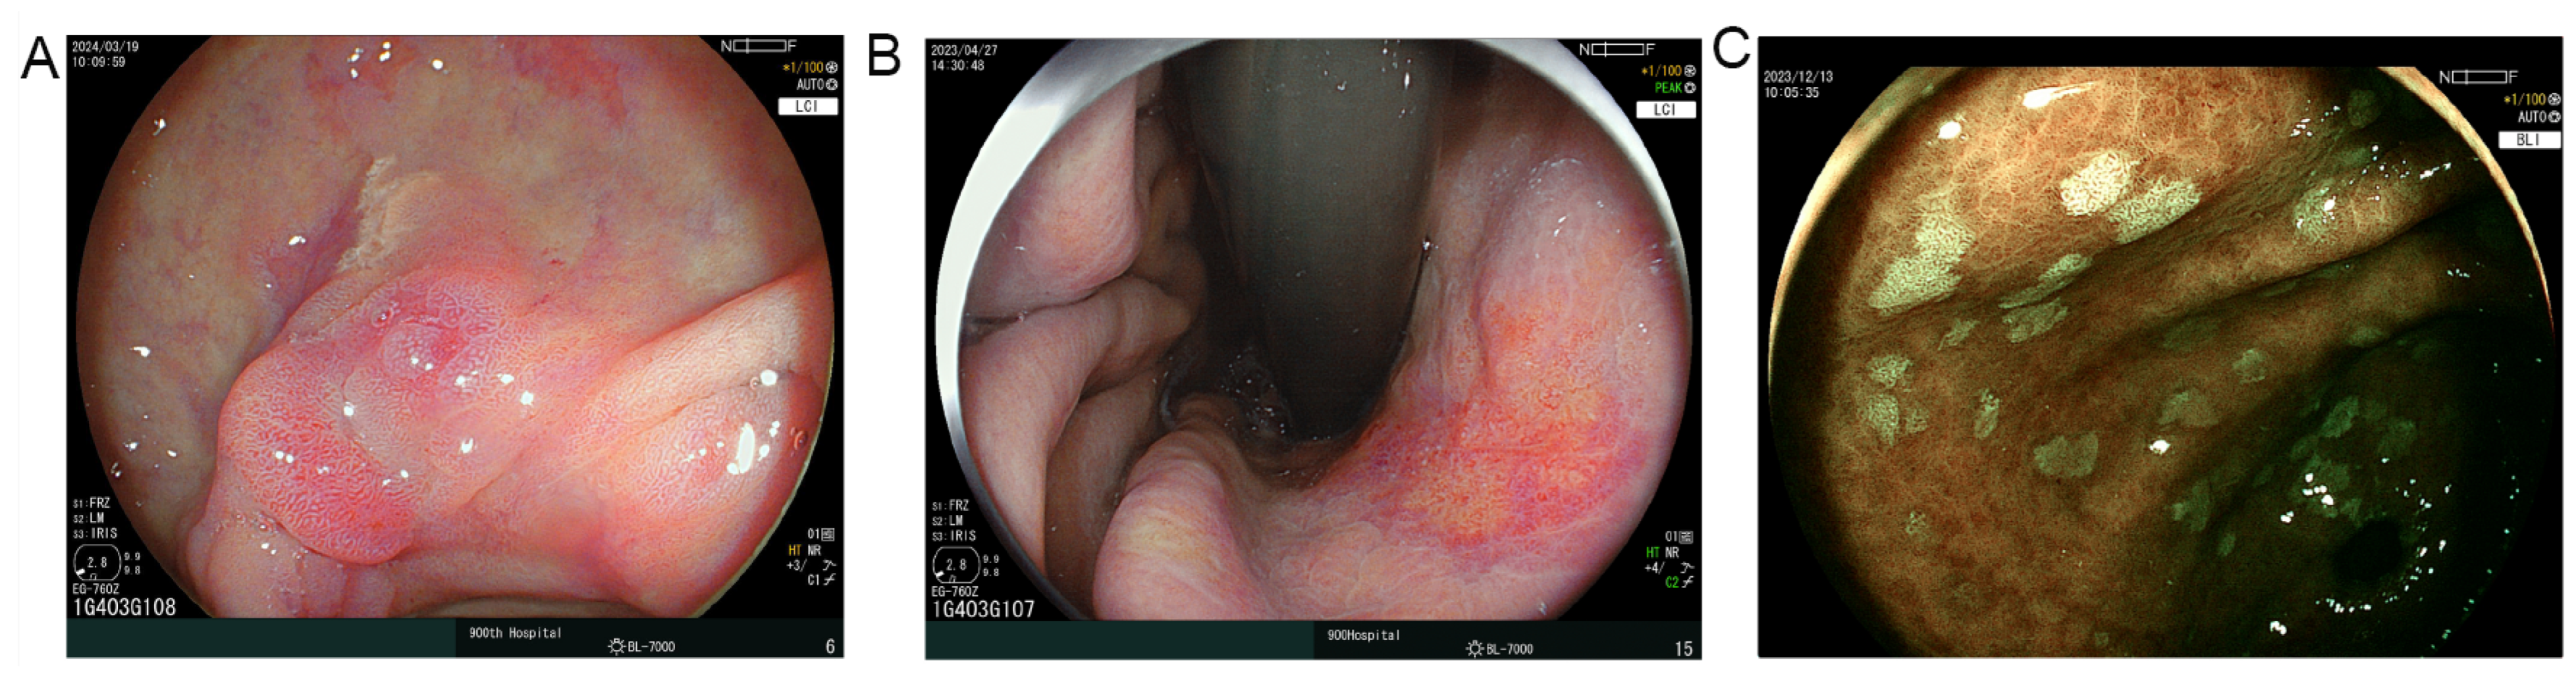

2.4. Endoscopic Assessment